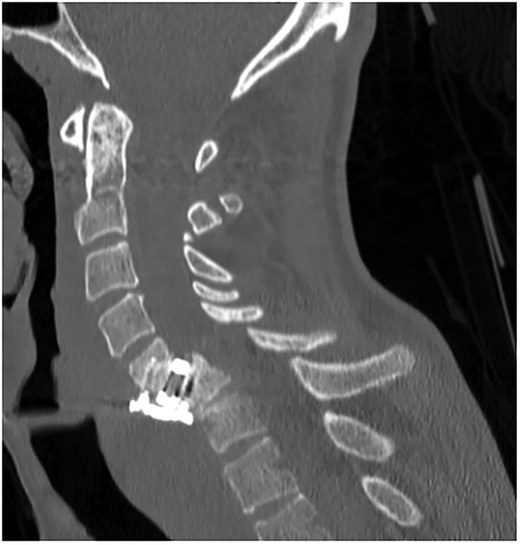

A 35-year-old male presented with a month-long history of dysphagia, severe headache, and posterior neck pain that radiated to the occiput. His medical history was significant for cervical surgeries, including an anterior cervical discectomy and fusion (ACDF) at C5/C6 one year and two months ago (Fig. 1). Shortly thereafter, the patient underwent revision surgery along with posterior plating from C5 to T1 due to osteomyelitis, worsening cervical deformity, and retropharyngeal abscess (Fig. 2). Initial workup included a noncontract computed tomography (CT), demonstrating increased gas density at C6 corpectomy site and post cricoid region (Fig. 3). A swallow study was obtained based on suspicion of a perforation and demonstrated extraluminal leakage of contrast posteriorly at the C6 level, consistent with initial CT (Fig. 4). Surgery included removal of the anterior and posterior hardware and esophageal repair. Although initially the esophageal injury was suspected to be related to the hardware, intraoperatively, it was found the instrumentation was not in communication with the esophagus. This confirmed the perforation was unrelated to direct injury from the cervical hardware construct, which was intact. The esophagus was repaired with a pectoralis flap. The postoperative course was uneventful, and the patient was discharged home after one week. The patient later died due to severe complications of substance abuse unrelated to the operation.

Initial sagittal CT without contrast after patient presented with symptoms of esophageal injury demonstrating increased gas density at the site of C6 corpectomy and post cricoid region.